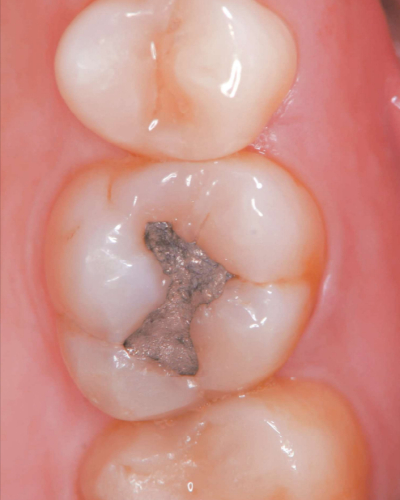

60 歳の男性。上顎左側第一大臼歯の修復物表面の粗造感を主訴として来院した。45 年前に齲蝕治療のため直接修復を受けたという。エックス線検査の結果、⎿6に齲蝕や修復物の破折を認めなかった。歯髄電気診で生活反応を示した。初診時の口腔内写真を別に示す。

適切な処置はどれか。1つ選べ。

a. 修復物の研磨

b. メタルインレー修復

c. レジンコーティング

d. コンポジットレジン修復

e. フッ化ジアンミン銀塗布